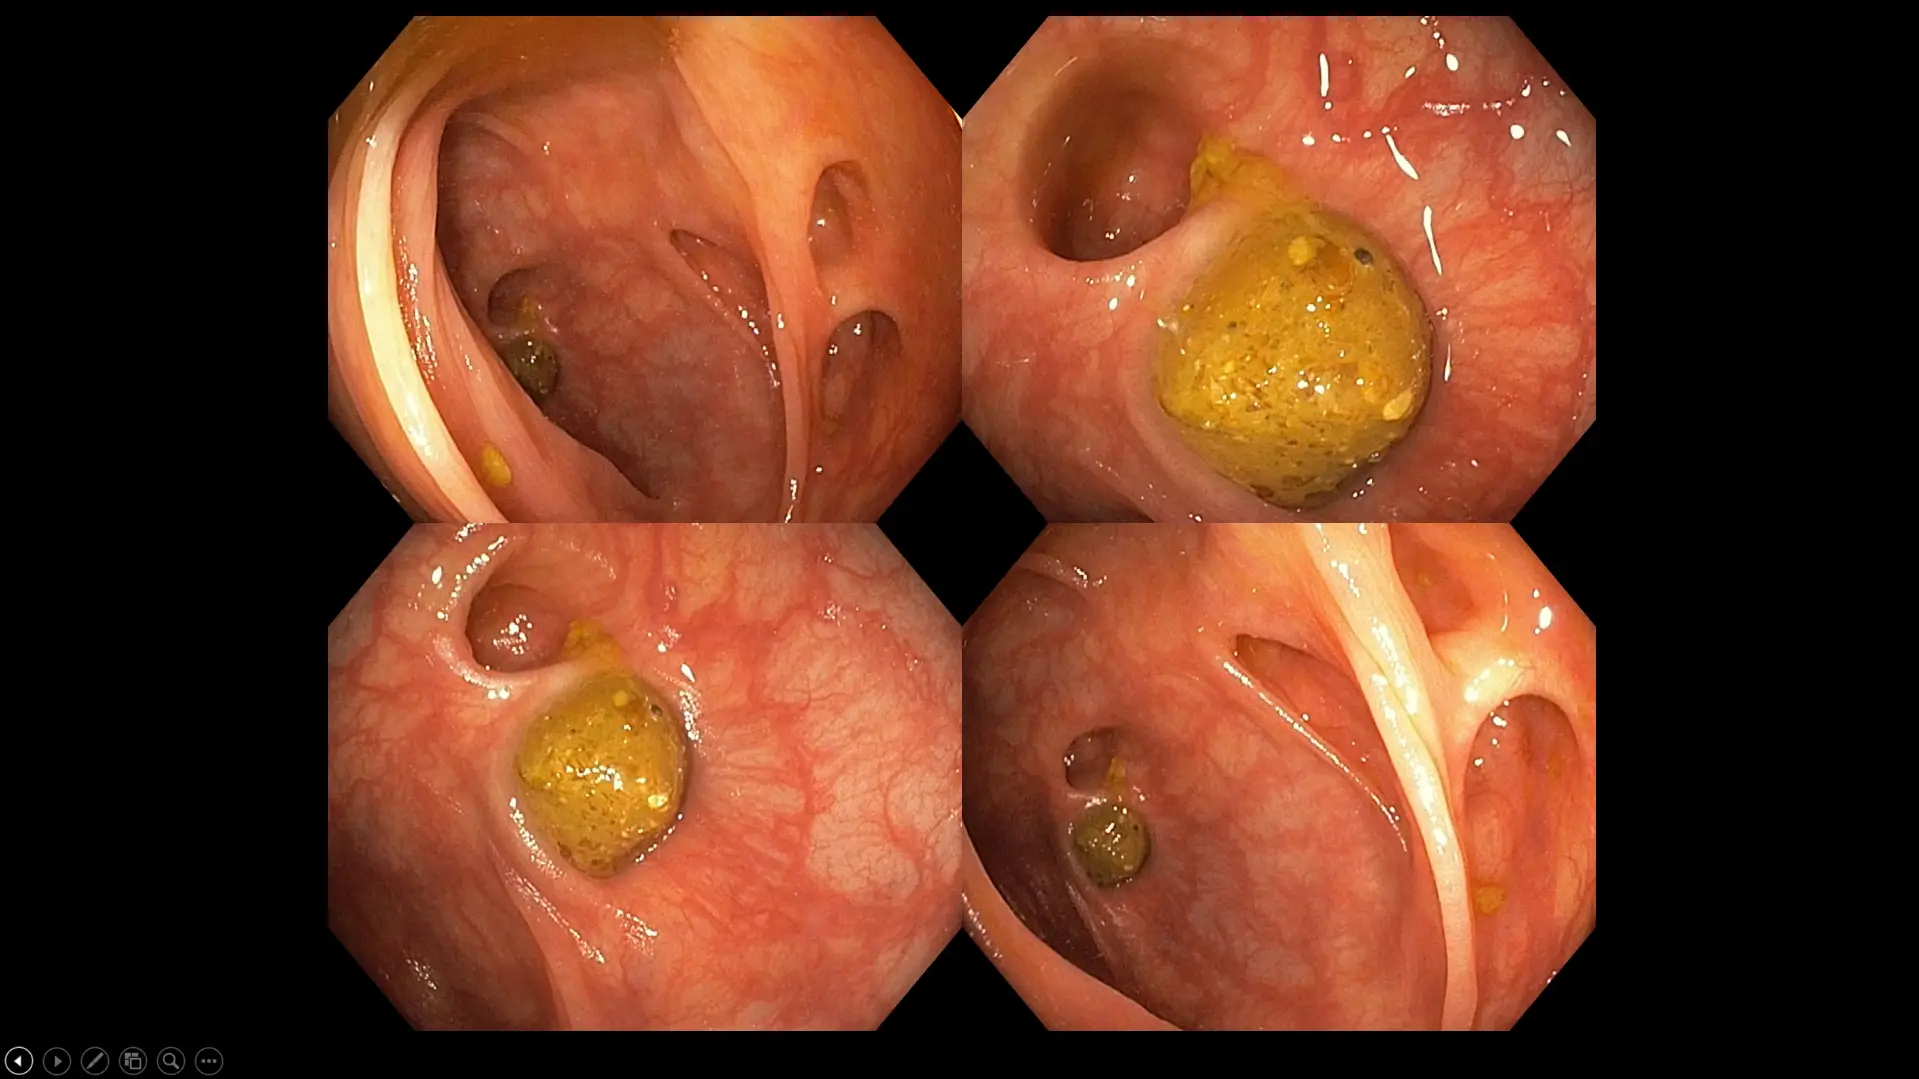

Figure 10: A case illustrating diverticular disease of the large bowel with impacted stools. Our patient experienced frequent abdominal cramps hours after a heavy meal, along with bloating and constipation. Note the varying sizes of the diverticular orifice, which range from as small as 1 mm in some patients to as large as 10 cm in extreme cases.